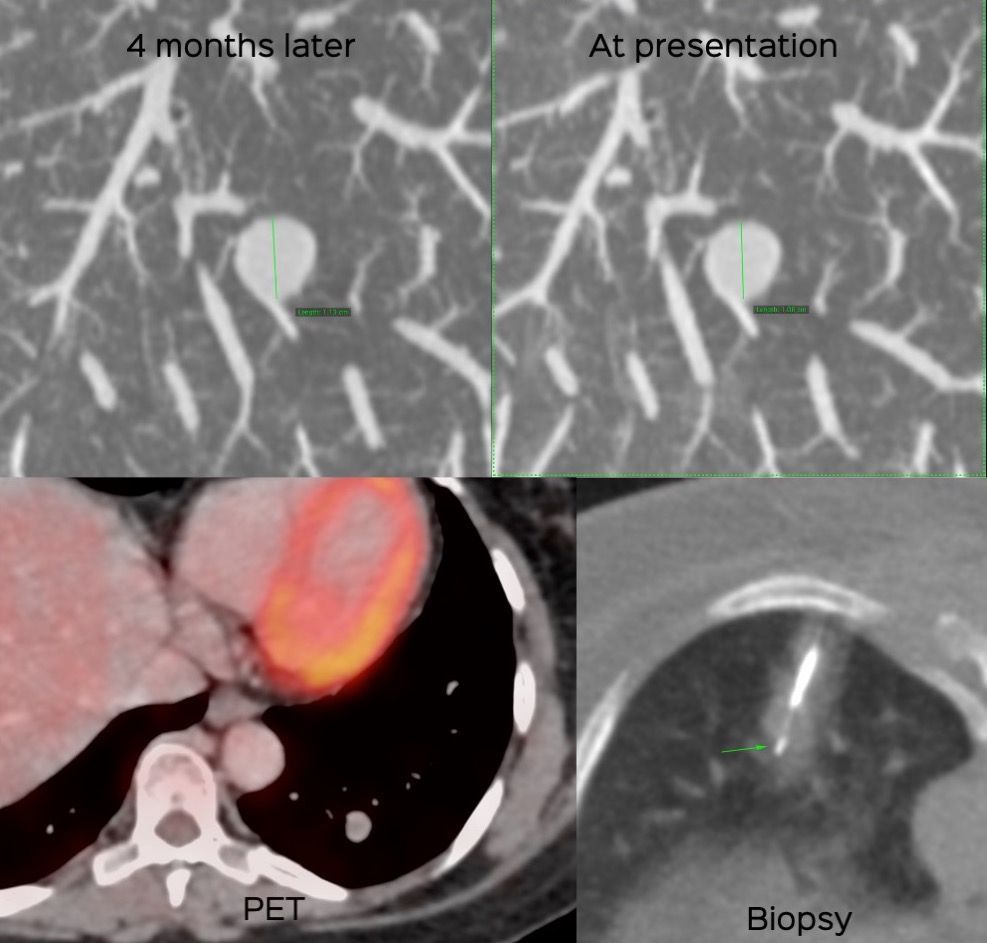

Case 31: The Curious Case of an Incidentally Detected Lung Nodule in a Middle-Aged Woman Paid Members Public

54-years old woman with an incidentally detected growing lung nodule and an unusual diagnosis